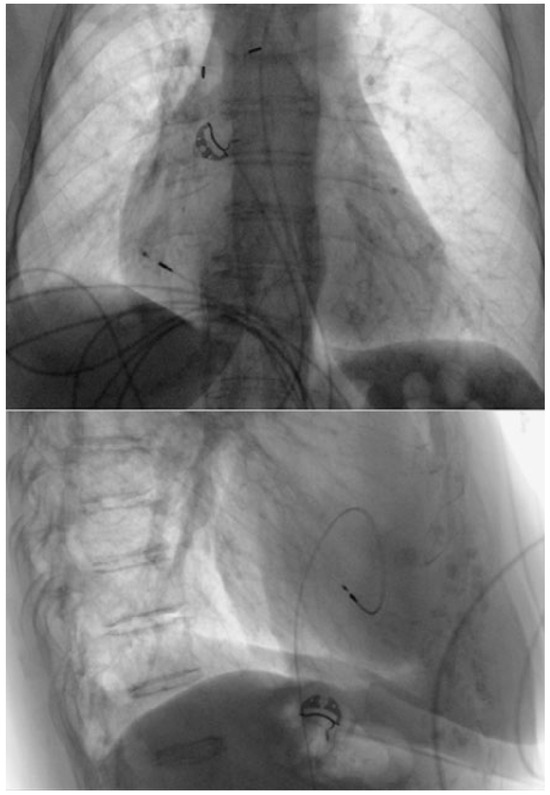

Standard Pacemaker Implantation via Femoral Venous Access

Pacemaker implantation via the femoral vein has been described since the 1980s. This technique is not very well known, but may be useful in some circumstances. We describe a case of a patient with sinus dysfunction without superior venous access, in...